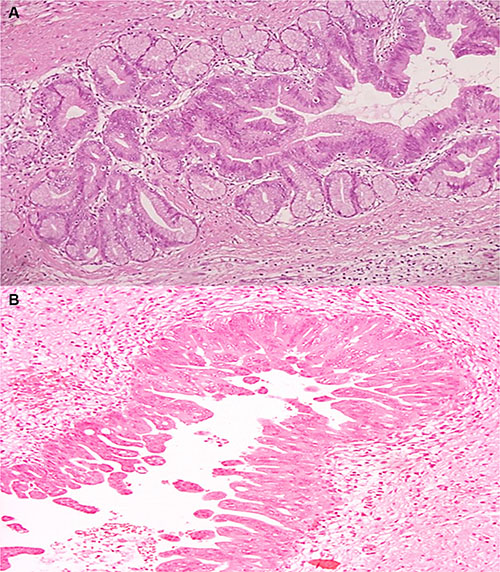

A total of 20 surgical specimens of IPMN were collected and classified according to WHO 2010 classification. Of the 20 IPMNs, nine (45%) were multifocal, seven (35%) were in the pancreatic head and four (20%) involved pancreatic tail. Macroscopically 14 samples (70%) were mixed-type, while 4 (20%) branch-duct type and 2 (10%) main-duct type. Dysplasia was low-intermediate in 7 cases, while high grade dysplasia was found in 13 out of 20 samples (Figure 1A–1B). In 4 IPMNs (20%) micro-invasive carcinoma areas were identified (< 1 mm), while two (10%) were associated with an invasive carcinoma (Table 1).

Figure 1: (A–B) Hematoxylin and eosin stained sections of IPMN. (A) Microscopic finding of the resected specimen demonstrates pancreatic branch duct with low-intermediate-grade gastric type IPMN (H&E ×20). (B) Microscopic finding of the resected specimen demonstrates pancreatic main duct with high-grade pancreatobiliary-type IPMN (H&E ×20).